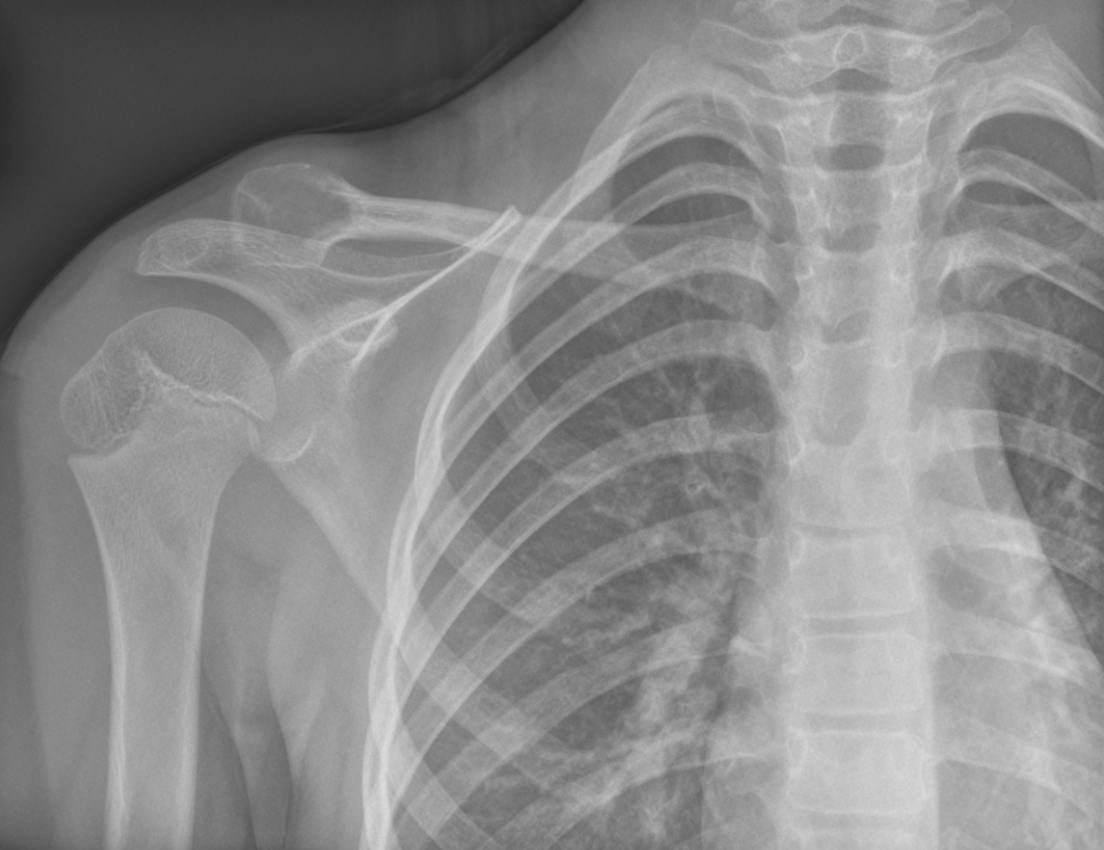

Aneurysmal Bone Cyst (ABC) of Clavicle